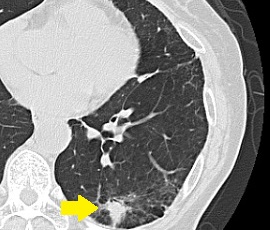

CT画像

CTガイド下針生検